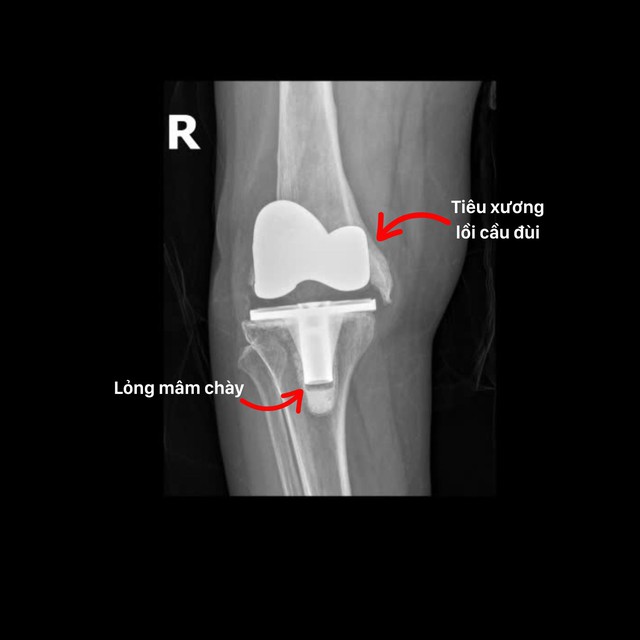

Biến chứng tiêu xương lồi cầu đùi và lỏng mâm chày sau thay khớp gối.

"Đây là trường hợp hiếm gặp bởi bệnh nhân bị mất hoàn toàn phần lồi cầu xương đùi, không còn điểm tựa để cố định khớp gối mới. Phẫu thuật viên phải thay lại khớp gối đồng thời tái tạo lại lồi cầu xương đùi (đầu dưới xương đùi) để tạo độ vững và giúp khớp vận động linh hoạt. THS.BS Trương Xuân Quang cho biết.

Chia sẻ về quá trình phẫu thuật, BS Quang nhấn mạnh: Quá trình phẫu thuật chúng tôi đã tháo toàn bộ khớp nhân tạo cũ, tái tạo lồi cầu bằng xi măng sinh học và cố định tạm bằng kim Kirschner. Khớp gối nhân tạo mới được chọn là loại chuôi dài, bám sâu vào ống tủy, giúp khớp ổn định và cải thiện biên độ vận động. Đồng thời tối ưu chi phí so với ghép xương hoặc sử dụng bộ khớp lồi cầu nhân tạo chuyên biệt".